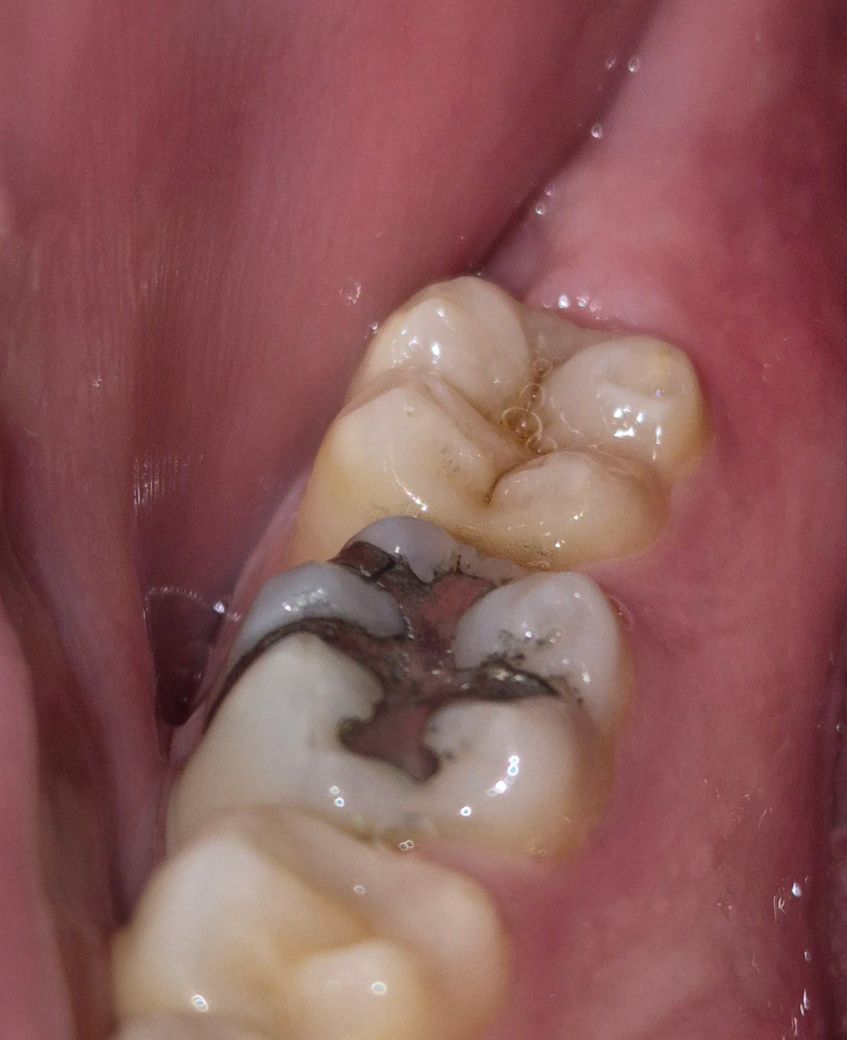

찬걸 먹거나 뭘섭취할때 시린통증이있어서 사진을찍어보니 충치가생긴거같기도하고 때운게 깨진거같기도하더라구요 이사진으로 충치를 알수있을까요?

• 1번 째 사진

사진상에 명확히 충치로 보이는 것은 보이지 않습니다. 사진으로는 워낙 불명확하니 치과 한번가보시는 게 좋겠습니다.

해당 사진에서 충치가 발생이 의심되는 부분이 있습니다. 빠른시일내에 치과에 방문하여 상태를 확인하고 치료를 받길 권합니다.

사진으로는 정확한 충치 여부를 확인하기 힘들어 보입니다. 앞에 있는 아말감은 부분적으로 깨져 있는 듯 보입니다. 치과 수복물이 깨질 정도의 강한 힘이 가해지면 치아에 불편감이 있을 수 있으니 치아에 가해지는 힘을 줄여 보는 것을 권유 드립니다

첫번째 큰 어금니 떼운게 깨지기도 했고 두번째 큰 어금니 충치도 관찰됩니다 시린증상은 위 2개 상황과 모두 연관된것 같습니다

현재 사진만으로는 정확히 알 수 없으며 지금 나타나는 증상이 단순히 충치 때문인지 아닌지 판단에도 어려움이 있습니다. 정확한 진단을 위해서는 x-ray 및 다각도적인 평가를 받아보셔야 하며, 지속적으로 불편감이 있다면 다시 한 번 치과 방문 후 검사를 해보시길 바랍니다.